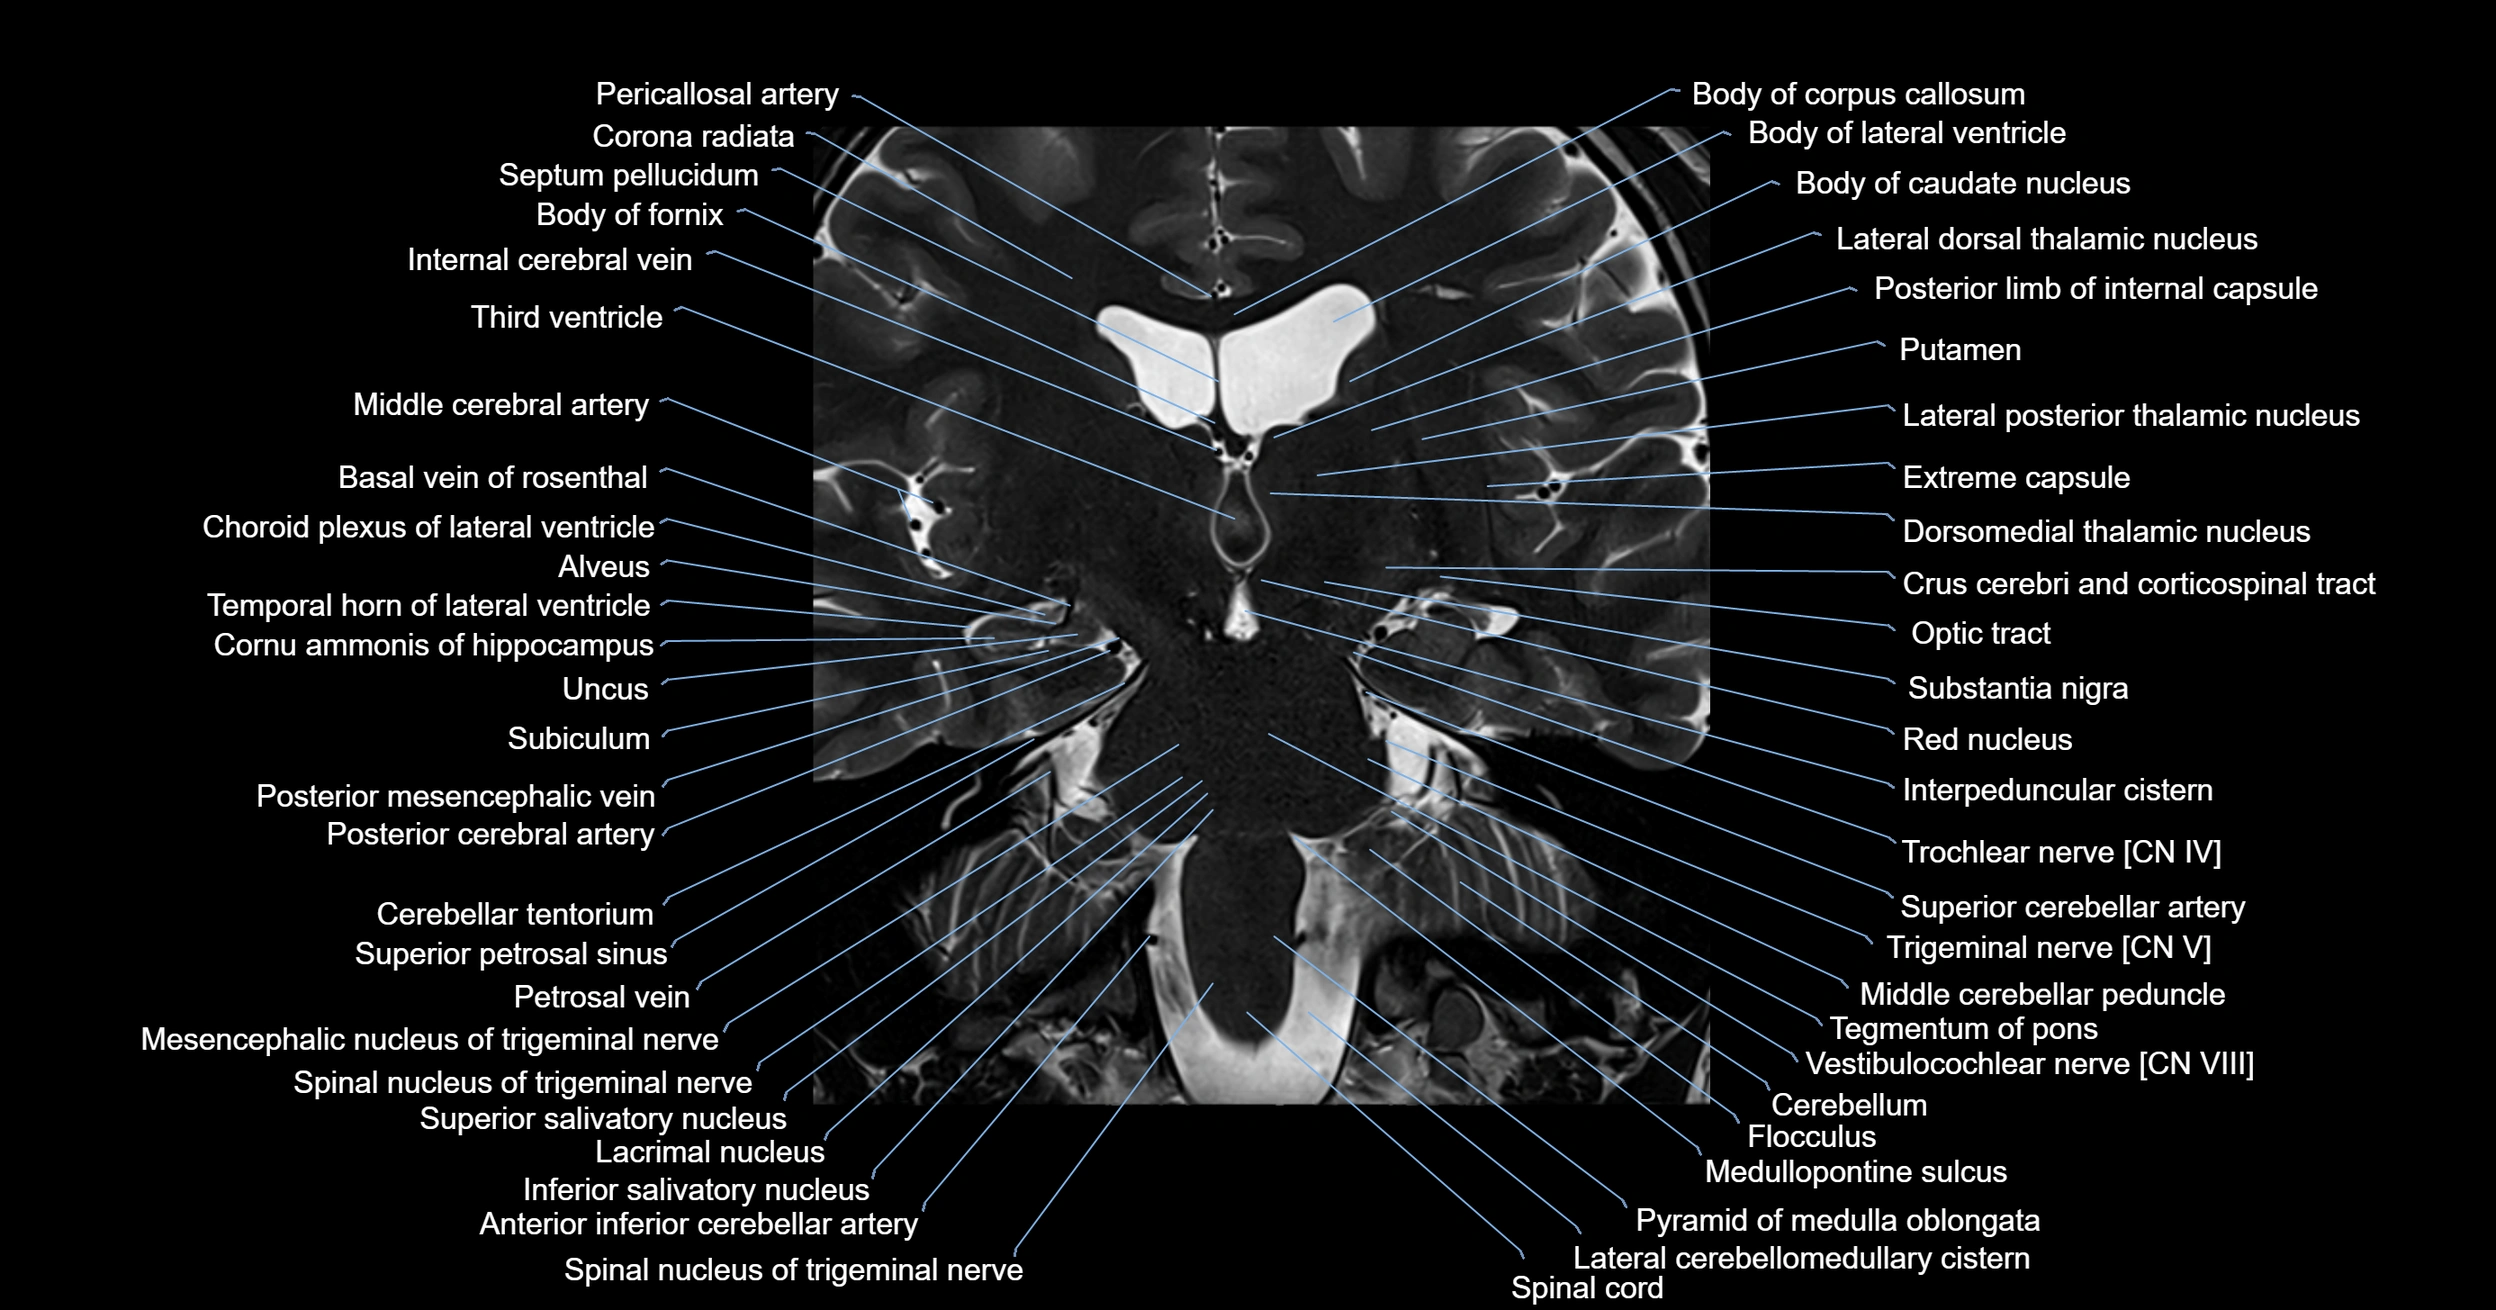

- Alveus

- Basal vein of rosenthal

- Body of caudate nucleus

- Body of corpus callosum

- Body of fornix

- Body of lateral ventricle

- Choroid plexus of the lateral ventricle

- Corona radiata

- Crus cerebri

- Facial Nerve (Cranial nerve VII)

- Flocculus

- Inferior salivatory nucleus

- Internal cerebral vein

- Lacrimal nucleus

- Lateral pontine vein

- Medial longitudinal fasciculus

- Medullopontine sulcus

- Mesencephalic nucleus of trigeminal nerve

- Middle cerebellar peduncle

- Pericallosal artery

- Petrosal vein

- Posterior limb of internal capsule

- Posterior mesencephalic vein

- Putamen

- Pyramid of medulla oblongata

- Red nucleus

- Spinal cord

- Spinal nucleus of trigeminal nerve

- Substantia nigra

- Superior cerebellar artery

- Superior cerebellar peduncle

- Superior petrosal sinus

- Superior salivatory nucleus

- Temporal horn of lateral ventricle

- Trochlear nerve (Cranial nerve IV)

- Vestibulocochlear nerve (Cranial nerve VIII)